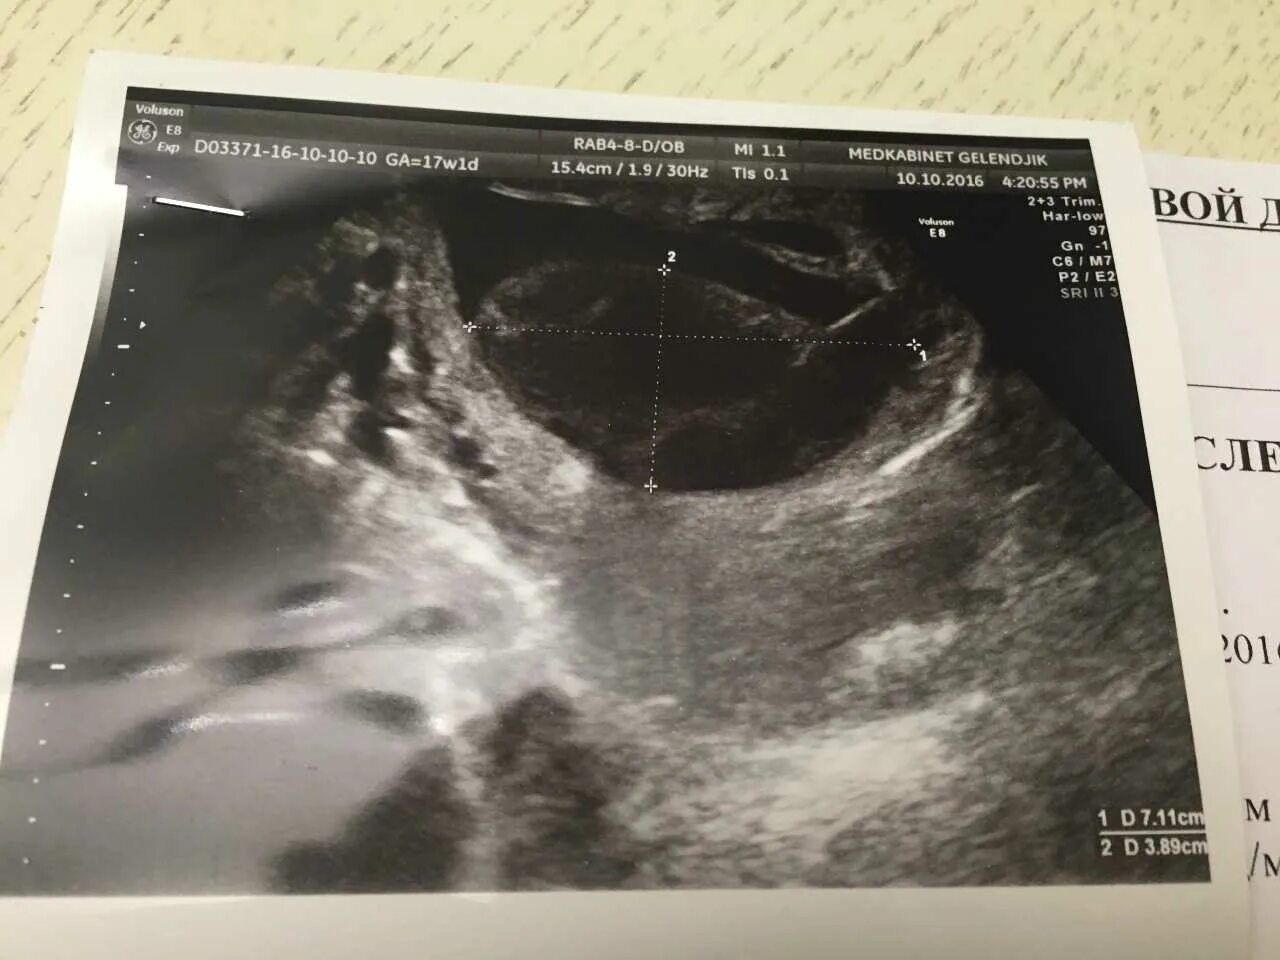

Плацента на 6 неделе беременности